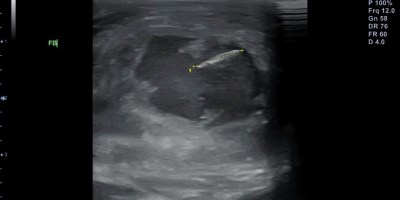

Interventional Radiology(Επεμβατική ακτινολογία), Uncategorized